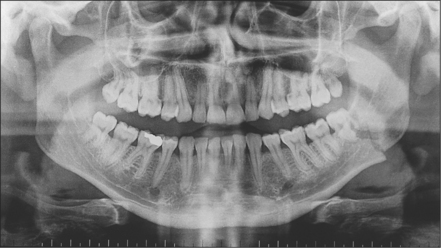

mid-face: two occipitomental views at different angles (Fig. 13.6)

tooth-bearing areas of the jaws: orthopantomogram and posteroanterior (Figs 13.7, 13.8)

image

Fig. 13.7 Orthopantomogram of fractured mandible.

Radiographs may be necessary not only to reach a diagnosis but also to inform treatment decisions, for example, about where bone plates should be applied. They also commonly reveal injuries which may not need treatment, for example, undisplaced or minimally displaced fractures, medial blow-out fractures of the orbit and comminution of the mid-face. Radiographs provide much more detailed information on hard-tissue injuries than the clinical examination so they may, for example, show fractures of the roots of teeth and signs of associated soft-tissue abnormality, such as herniation of orbital contents into the maxillary antrum (Figs 13.9, 13.10).